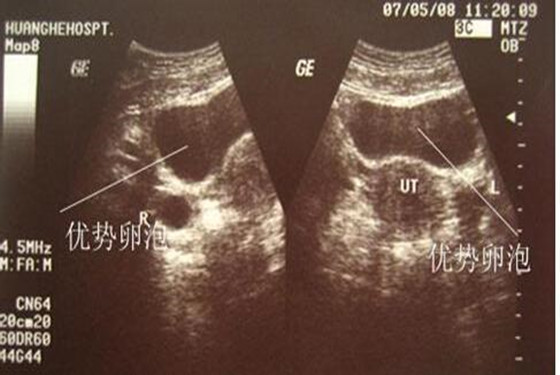

若要问卵泡监测什么时候做最合适,医生建议根据具体的月经周期进行监测,每个女性的月经周期有所不同,排卵的时间也各自有差异。卵泡监测一般在月经周期第9-10天时进行,每隔1-2天去医院用B超监测一次,医生通过几次B超检测后,就可以看到卵泡慢慢长大、成熟以及排卵的全过程。至于,优势卵泡什么时候会出现,这是因人而异的,通常月经周期28天的女性,在监测的第9-12天内优势卵泡会出现。

卵泡监测,不是一个短期能看到结果的检查,做这种检查时一定要注意连续性,不能一看到优势卵泡出现就停止监测,一定要坚持到确认排卵或卵泡发育不良后为止。另外,卵泡监测不是做一次就可以的,女性要根据自己的月经情况,从来月经第1天开始直到第11天,隔天需要去医院用B超进行监测,这个过程很漫长,可能长达三个月之久,这样医生才能找出你的规律哦。